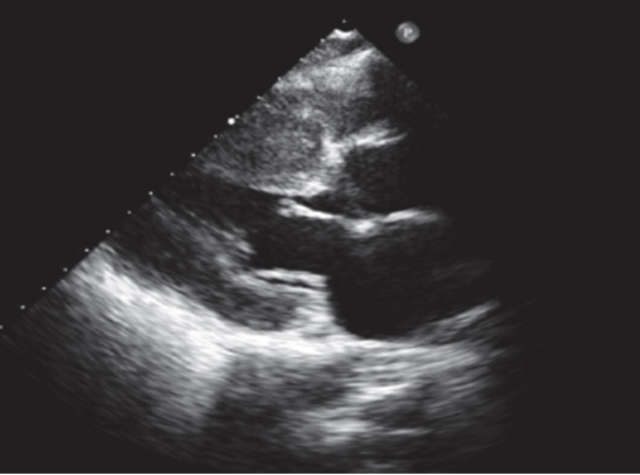

超声心动图左室长轴提示左室壁非对称性肥厚

想要精准揪出这颗“胖心脏”,超声心动图是首选的“火眼金睛”。这项无创、便捷又经济的检查,能清晰测量心室壁厚度,判断左心室流出道是否存在梗阻及梗阻程度,还能全面评估心脏收缩舒张功能和瓣膜状态。根据诊断标准,只要超声或磁共振检查发现左心室舒张末期任意部位室壁厚度≥15mm,或有家族遗传背景者(致病基因检测阳性、家系成员患病)的心室壁厚度≥13mm,即可确诊。